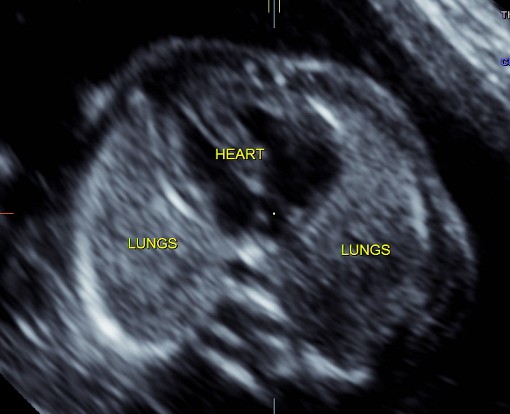

the following two pictures establish the normal situs